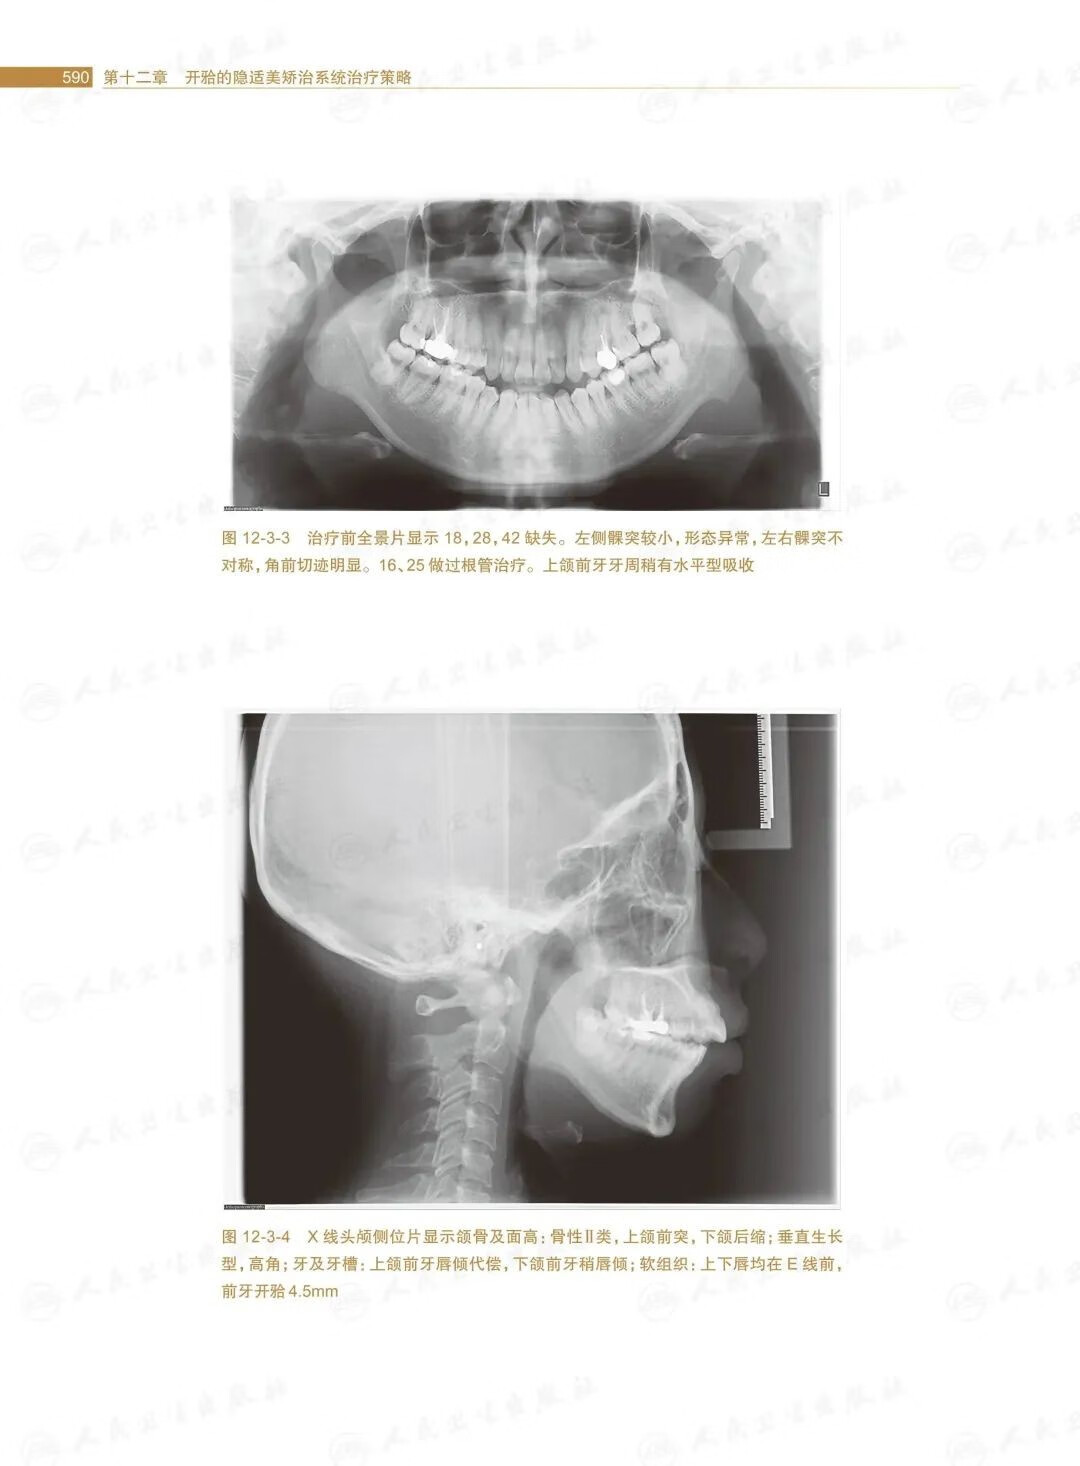

第三節安氏Ⅱ類開的矯治策略/588

第四節安氏Ⅲ類開的矯治策略/601